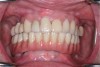

Fig 21. Postoperative close-up retracted facial view and right lateral view of the patient with her full zirconia implant-supported restoration that was salvaged using the fixed locator system.

Figure 21

Fig 22. Postoperative close-up retracted facial view and right lateral view of the patient with her full zirconia implant-supported restoration that was salvaged using the fixed locator system.

Figure 22

Delivering the Salvaged Full Zirconia Prosthesis

The retrofitted and salvaged full zirconia prosthesis was then reseated; proper and full seating of the green retentive ball was confirmed by an audible clicking sound. The prosthesis was then secured to the screw-retained abutments. The screw access holes were then sealed using polytetrafluoroethylene tape and either pink (eg, in gingival areas) or tooth-colored (eg, premolar area) acrylic material (Figure 21 and Figure 22). Considering the patient's aggressive grinding habit, her occlusal night guard was adjusted to ensure a correct fit to the new prosthesis.